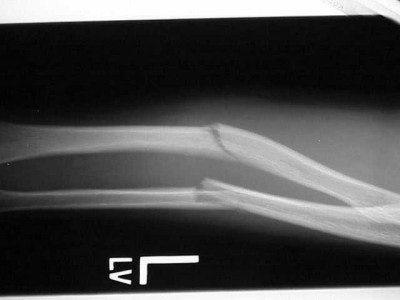

In figure 3 there is an obvious midshaft fracture of the forearm on the AP view. The film was shot with the forearm in a position of comfort on the child’s lap. On the attempted lateral, figure 4, we see that because of the deformity, it is not a true lateral. It, again, was shot cross-table with the film braced between the child and his forearm.